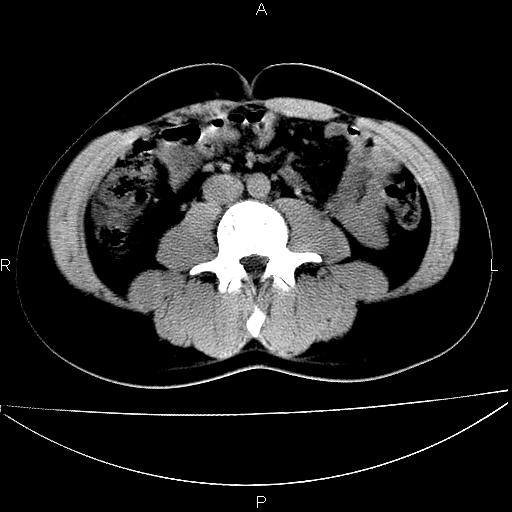

男 25岁 自述 尿频尿急,排尿困难20多天.无腰痛, b超说左肾盂轻度积水,左输尿管上端扩张.未见结石影. ct我看双侧肾盂轻度积水,双输尿管上端都扩张,大家看看能看见结石吗?

未见明确输尿管结石,mru效果还好

双侧输尿管上端扩张,未见明确结石,可进一步ivp检查。

双肾盂及双输尿上段轻度积水,双输尿管未见明显结石影。

肾外肾盂,必要时+c